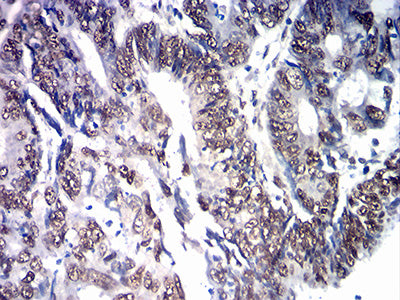

分类: 科研抗体货号: 31877别名: FCC2; COCA2; HNPCC; hMLH1; HNPCC2应用: WB,IHC,FCM反应种属: Human